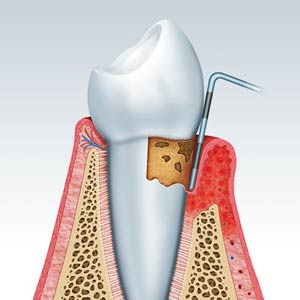

کورتاژ لثه (خراشیدن لثه)

این تکنیک جراحی لثه شامل خراشیدن بافت ناسالم از بخش عفونت کرده لثه و در نهایت التیام لثه سالم باقی مانده است.